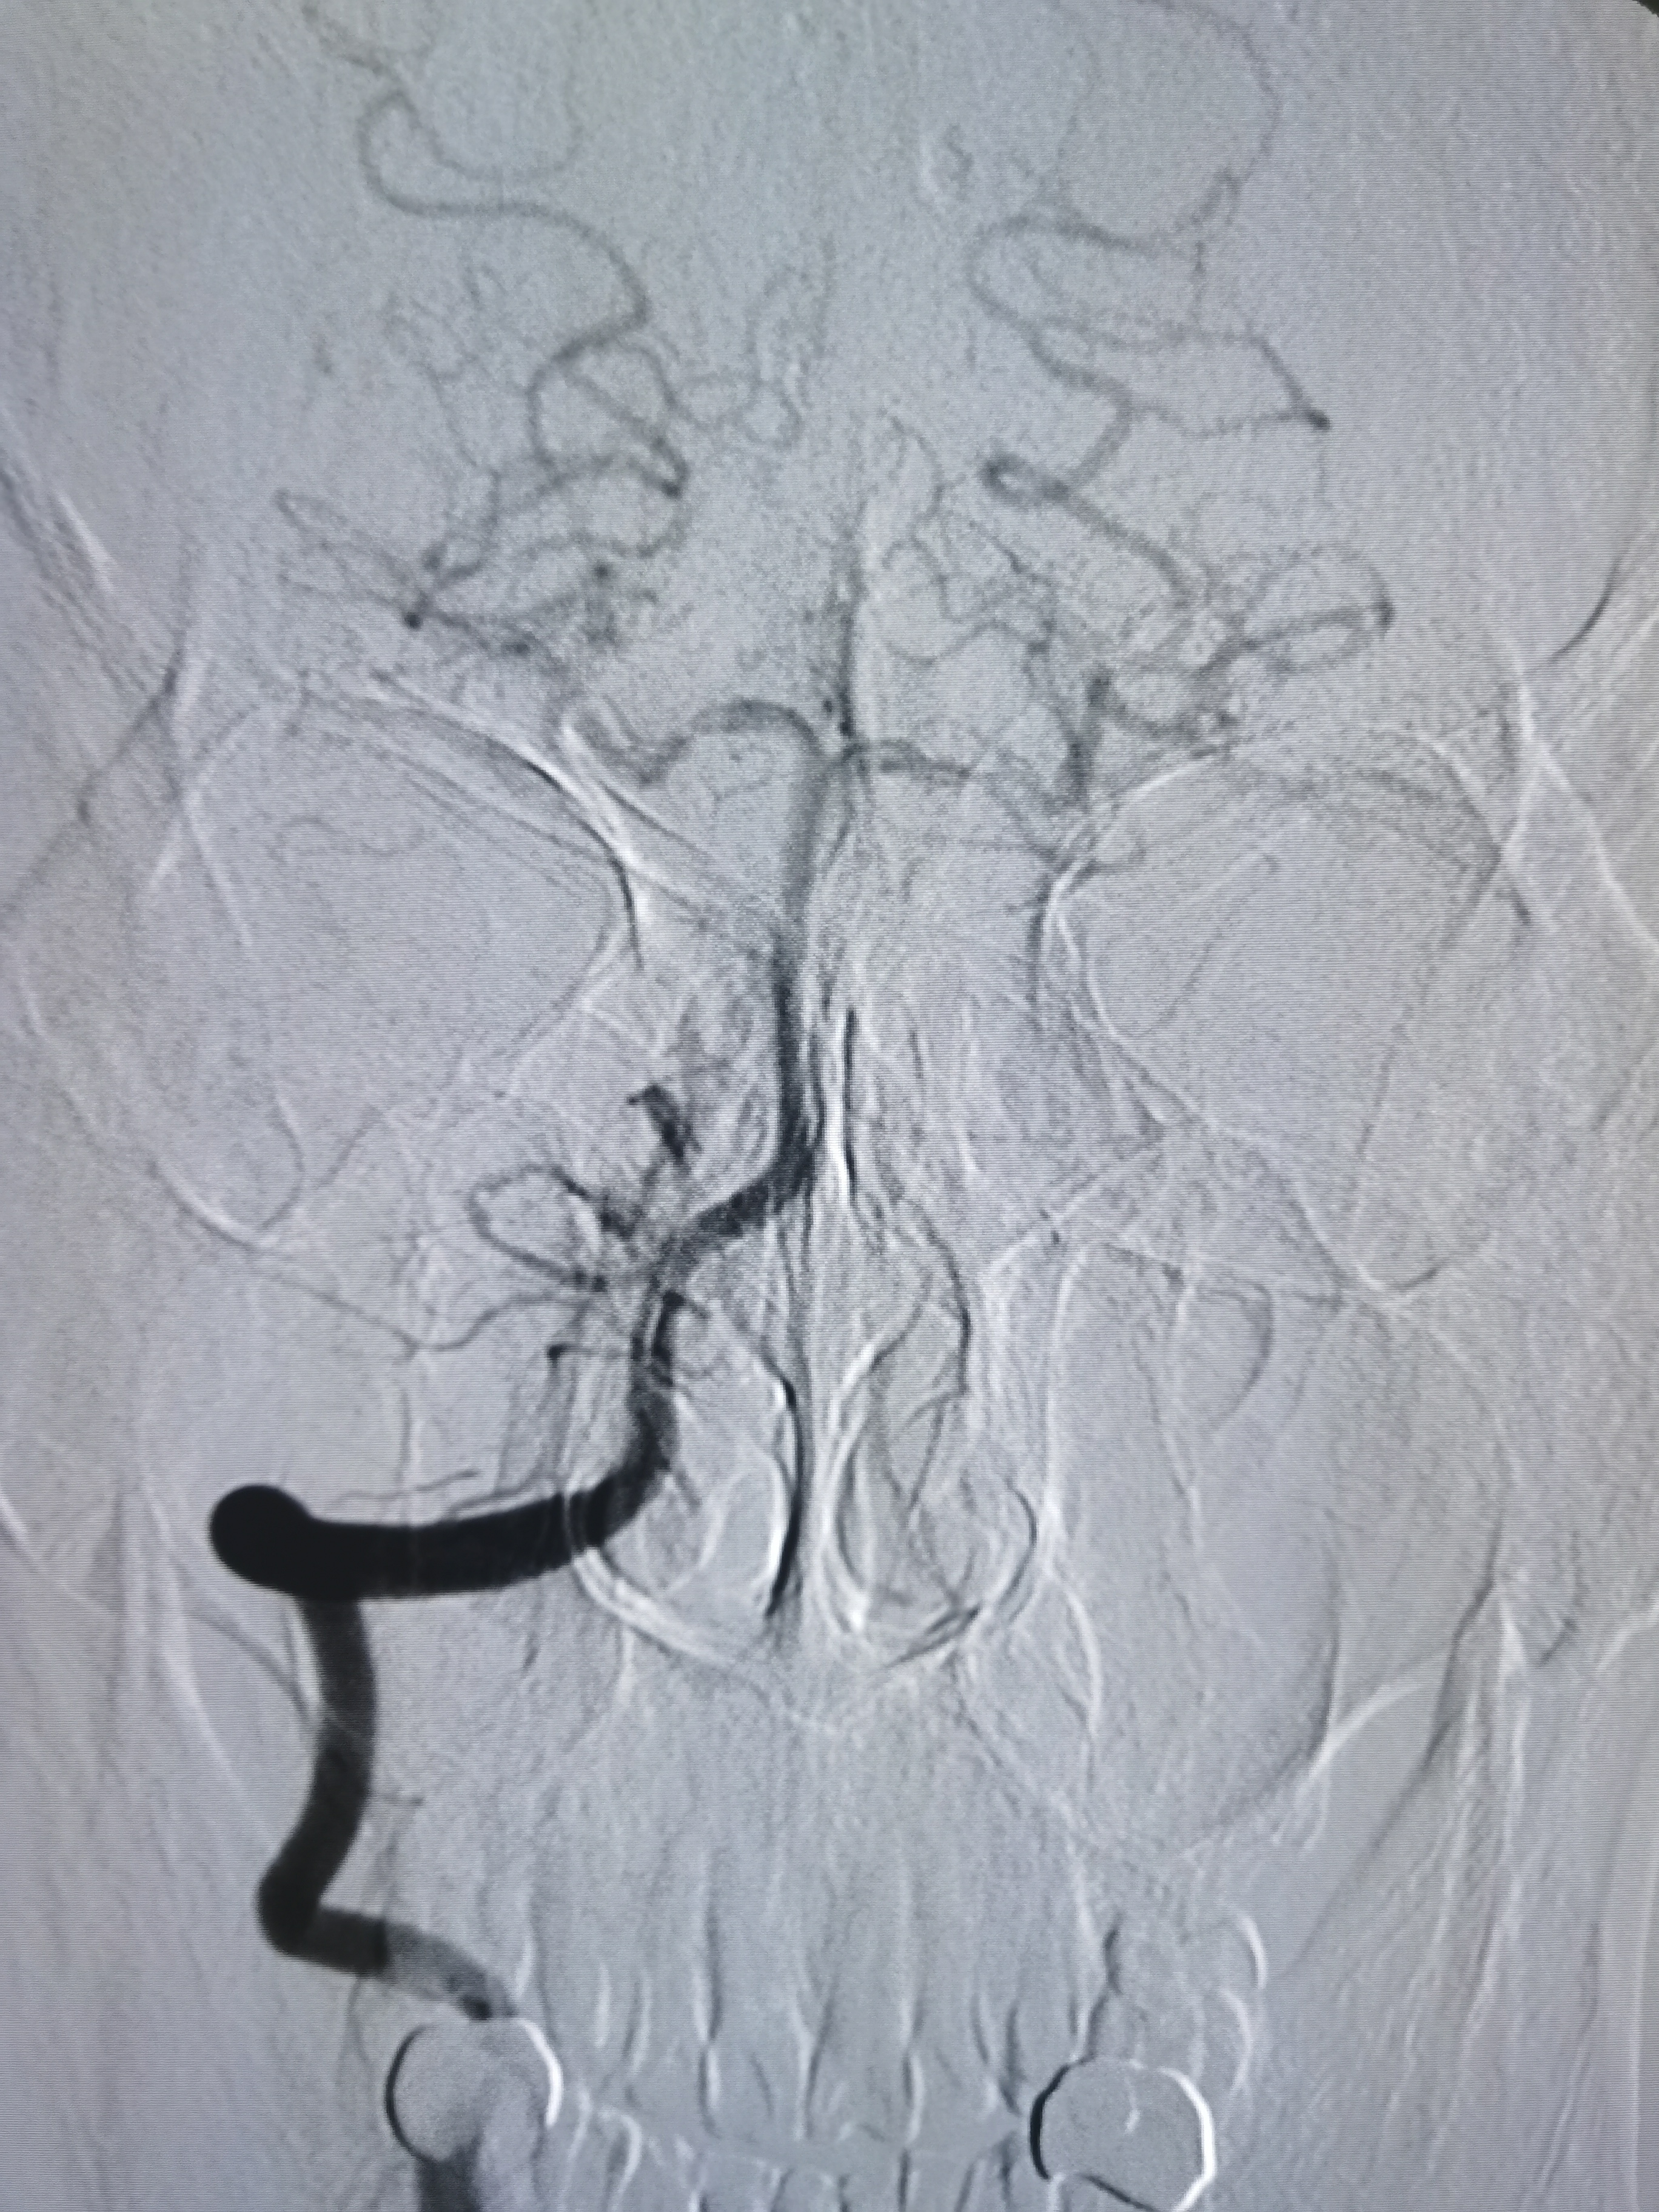

正位见左侧大脑中动脉闭塞。

动脉晚期可见左侧大脑中动脉M2段返流。

造影分析:

患者左侧大脑中动脉M1起始段闭塞,动脉晚期可见返流至M2显影,考虑新近闭塞,具备介入开通指征,手术风险在于血管夹层,破裂及急性血栓形成,向患者家属详细交代病情后,家属积极要求介入治疗。

扩张后造影见血管再通,血流通畅。

侧位造影见血流通畅。

观察15分钟后造影血流通畅,未见夹层及明显弹性回缩。

复查造影见颅内狭窄解除,血流通畅,遂未再植入支架,撤出导丝及各级系统,结束手术。患者麻醉苏醒顺利,无新发神经系统症状,给予替罗非班持续泵入,监测生命体征,控制血压避免再灌注损伤。